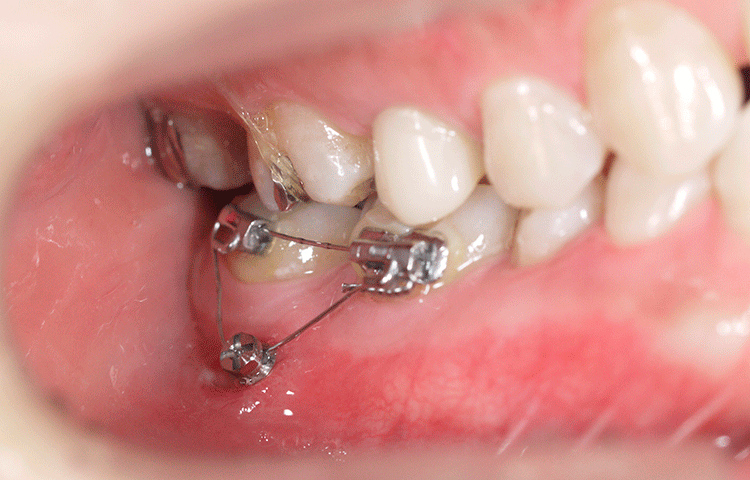

矯正用インプラント

矯正用インプラントによる矯正治療は、従来型の矯正治療法では、今まで困難とされてきた方向への歯の移動が可能となり、矯正治療期間を短縮できるなどのメリットもあります。

治療期間:1ヶ月